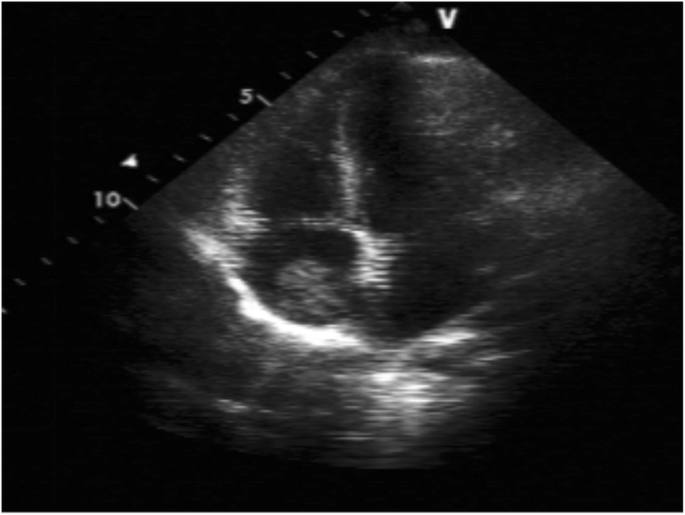

An 8-year-old female who presented with left rib pain, hematuria and fever was admitted to our hospital. The maximum temperature reached 39.9 °C, with no chills or rash. She was administered cefepime and azithromycin for 1 day, cefotaxime for 5 days, and methylprednisolone for 1 day. On physical examination, her general condition was poor, with eyelid and lower limb edema; coarse respiratory sounds and auscultation of blisters of both lungs were noted, and no other abnormal findings were present at that time. Laboratory findings were as follows: white blood cell count 6.32*109/L, neutrophil 0.48, lymphocyte 0.42, red blood cell count 3.40*1012/L, hemoglobin 93 g/L, and platelet count 48*1012/L. Her urine revealed 363.69 red blood cells/high-powered field (hpf), protein 3+, 5.1 white blood cells/hpf, erythrocyte sedimentation rate (ESR) 135 mm/h, C-reactive protein (CRP) 25.2 mg/L, albumin 17.6 g/L, total cholesterol 7.21 mmol/L, and urinary protein 3.2 g/24 h. Other laboratory findings included activated partial thromboplastin time (APTT) 138.7 s, direct antiglobulin test positive, ferritin 358.4 μg/L, D-dimer 4937.00 μg/L, and FDG 33.8 μg/ml. Serum showed C3 0.92 g/L (0.9–1.8), C4 0.17 g/L (0.1–0.4), ANA:anti-SSA-60 ±, anti-nRNP/Sm positivity, homogeneous 1:3200 positivity, dsDNA 1:10 positivity, antinucleoome antibody positivity, antimitochondrial M2 positivity, anticardiolipin IgM 12 U/ml (0–10), and anti-β2GPI 223 U/ml (0–20). Bone marrow biopsy revealed secondary anemia, and globular red blood cells accounted for 5.5%. However, respiratory pathogens, myocardial enzymes, mycoplasma pneumoniae/chlamydia antibodies, procalcitonin, folic aci, vitamin B12, reticulocytes, bacterial cultures of blood, stool, tuberculosis spots, Epstein-Barr virus, cytomegalovirus, ANCA were all negative. Hematuria location: urine abnormal red blood cell 60%, urine uniform red blood cell 40%. Bronchoscope results showed inflammation of the endobronchial membrane. Pulmonary CT revealed patchy high-density shadows in all lobes of the lungs, especially in the lower lobes of the lungs (Fig. 1). Color Doppler ultrasonography of the lower limbs ruled out deep vein thrombosis. Abdominal color ultrasound revealed abdominal effusion. Echocardiography showed a kind of round moderate echo with a diameter of approximately 2.0 cm that could be seen at the bottom of the right atrium near the opening of the inferior vena cava. The patient was diagnosed with right atrial thrombus (Fig. 2). Renal pathology using light microscopy revealed 52 glomeruli in the renal tissue; there were 52 glomeruli in the renal tissue, with slight proliferation of mesangial cells and mesangial matrix, swelling and slight proliferation of segmental foot nuclear endothelial cells, slight thickening of glomerular basement membrane and a large amount of phenophilin deposition in subepithelial cells. No microthrombi or crescents were observed, and a small amount of inflammatory cell infiltration dominated by neutrophils was found in some glomeruli. There was slight edema in the renal interstitium, and there was no renal tubular atrophy and obvious inflammatory cell infiltration and fibrosis. No obvious abnormalities were found in the arterioles. Immunofluorescence analysis was positive for IgA, IgM, IgG, C3, C4, and C1q deposited along the glomerular capillary wall and segmental mesangial area. The above features were consistent with membranous LN with mesangial proliferative LN (consistent with types V and II LN) (Figs. 3 and 4). Nephrotic syndrome is a common disease in children that is characterized by edema, massive proteinuria (>50 mg/kg.24 h), hypoproteinemia (<25 g/l) and hypercholesterolemia (>5.7 mmol/l). Our patient’s disease characteristics were consistent with those of nephrotic syndrome [1]. We continued to track the etiology of nephrotic syndrome, and the child had no family history of renal disease; therefore, we investigated secondary factors, including serology results that were positive for ANA and anti-dsDNA with low C3 levels. Although her platelets and hemoglobin levels were significantly lower than normal, she had no rash, arthralgia, photosensitivity, oral ulcer, or butterfly erythema, so a renal biopsy was performed, which suggested LN. The patient was finally diagnosed with SLE and LN. She was treated with pulse methylprednisolone for 3 days and IV diuretic with albumin, followed by oral steroids 1 mg/kg.d after 3 days, with rapid resolution of edema. Anticardiolipin IgM of 12 U/ml and anti-β2GPI of 223 U/ml were consistent with secondary APS. What was the cause of the space-occupying mass in the right atrium? At this point, as no clear etiological evidence was found, a repeated echocardiography indicated that the nature of the right atrial mass was a thrombus. The mass was reduced by anticoagulant therapy with heparin for 2 weeks. By 3 weeks, proteinuria decreased to 1.0 g/day, and by 16 weeks, she was in complete remission with < 0.5 g proteinuria. After 6 months of follow-up, the patient has remained in complete remission, but 2.5 mg of prednisolone is administered each day.

Systemic lupus erythematosus (SLE) is an autoimmune disease that can involve multiple organs. Its pathological manifestations are immune complex deposition and vasculitis changes. Lupus nephritis (LN) is a common manifestation of SLE. In the early stage of SLE, LN may show slight abnormalities in urine (microhematuria, albuminuria) [2,3,4,5], with nephrotic syndrome, hypertension, or renal failure [6, 7]. In this case, the child was diagnosed with nephrotic syndrome, and renal biopsy revealed LN. According to the International Society of Nephrology (ISN/RPS), LN is divided into six grades (grades I-VI) [8]. Nephrotic syndrome is usually associated with diffuse or membranous. LN [9]. However, membranous LN or mesangial proliferative LN is rare in children. Echocardiography revealed an occupying mass in the right atrium. The nature of the mass is usually a neoplasm, tumor, or thrombus. The neoplasms are most common on the valves, and no neoplasms were found by echocardiography. Scholars [10] have pointed out that myxoma is the most common cardiac tumor, is usually located in the left atrium, and is usually attached to the atrial septum. Cardiac myxoma is mostly found in the left atrium, which is mostly attached to the atrial septum, accounting for approximately 15% of the right atrium, while atrial thrombus is more common in the left atrial appendage. Thrombi in the right atrium are rare. How can an atrial thrombus and a cardiac myxoma be distinguished? In fact, the identification of the two is mainly determined using ultrasound, and generally speaking, the identification is not very difficult. Cardiac myxoma can be accompanied by blood flow fluctuations, but a thrombus generally is not. The shape of cardiac myxoma can change with the relaxation or contraction of the heart, but a thrombus will not. Anticoagulants can dissolve part of the thrombus, but cardiac myxoma cannot be dissolved by anticoagulants. The volume of the atrial mass was reduced in our patient after anticoagulation with heparin.